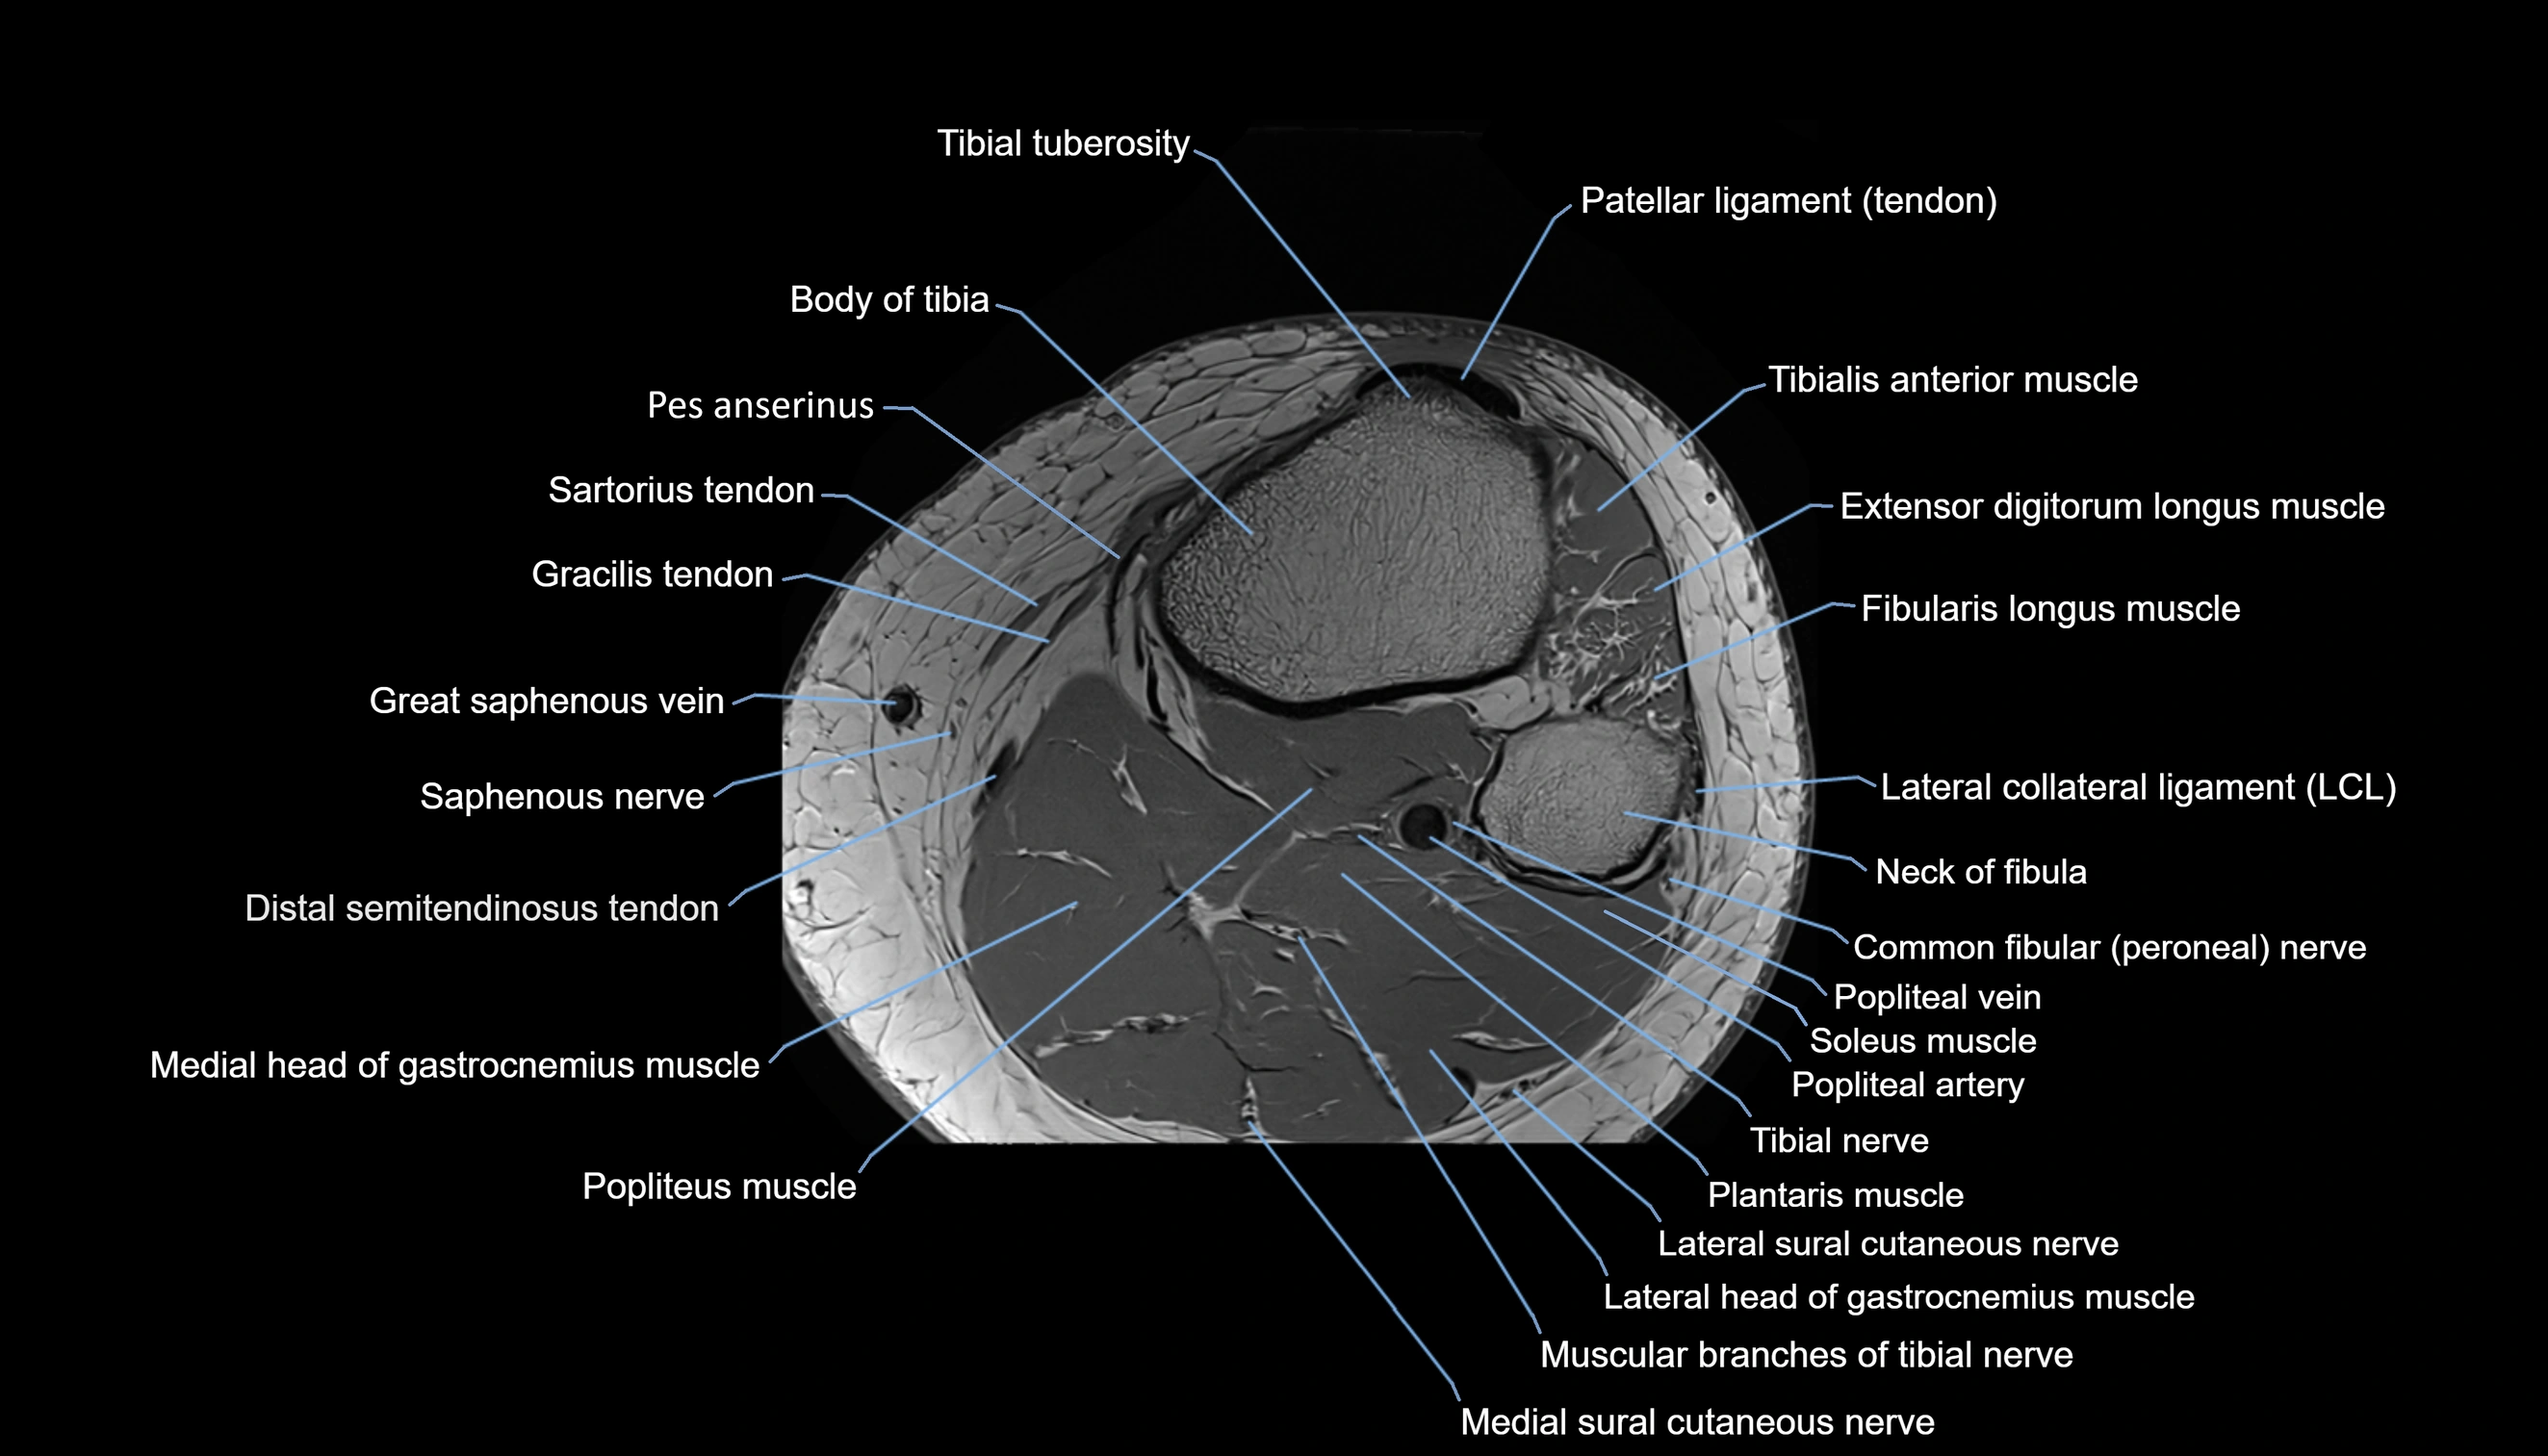

- Body of tibia

- Common fibular nerve

- Extensor digitorum longus muscle

- Fibularis longus muscle (peroneus longus muscle)

- Gracilis tendon (Distal)

- Lateral collateral ligament

- Medial head of gastrocnemius muscle

- Medial sural cutaneous nerve

- Muscular branches of tibial nerve

- Neck of fibula

- Popliteal artery

- Popliteal lymph nodes

- Popliteal vein

- Popliteus muscle

- Sartorius tendon (Distal)

- Soleus muscle

- Tibial nerve

- Tibial tuberosity

- Tibialis anterior muscle

- great saphenous vein